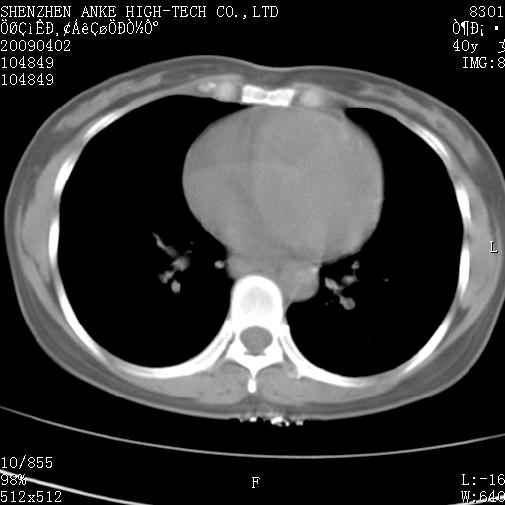

以下是引用随光逐影在2009-4-2 12:16:00的发言:[br]考虑左肺下叶背段继发性肺结核,结核球形成;建议追踪复查。

以下是引用gudu医生在2009-4-2 11:27:00的发言:[br]周围型肺癌

以下是引用卜一在2009-4-2 13:31:00的发言:[br][br] [br] 空洞壁厚不均 胸膜凹陷征。周围型肺癌可能 不排除干酪坏死型肺结核及坏死性肉芽肿。 [br] [br]支持!

以下是引用ct诊断高手在2009-4-2 13:04:00的发言:[br]空洞壁厚不均 胸膜凹陷征。周围型肺癌可能 不排除干酪坏死型肺结核及坏死性肉芽肿。